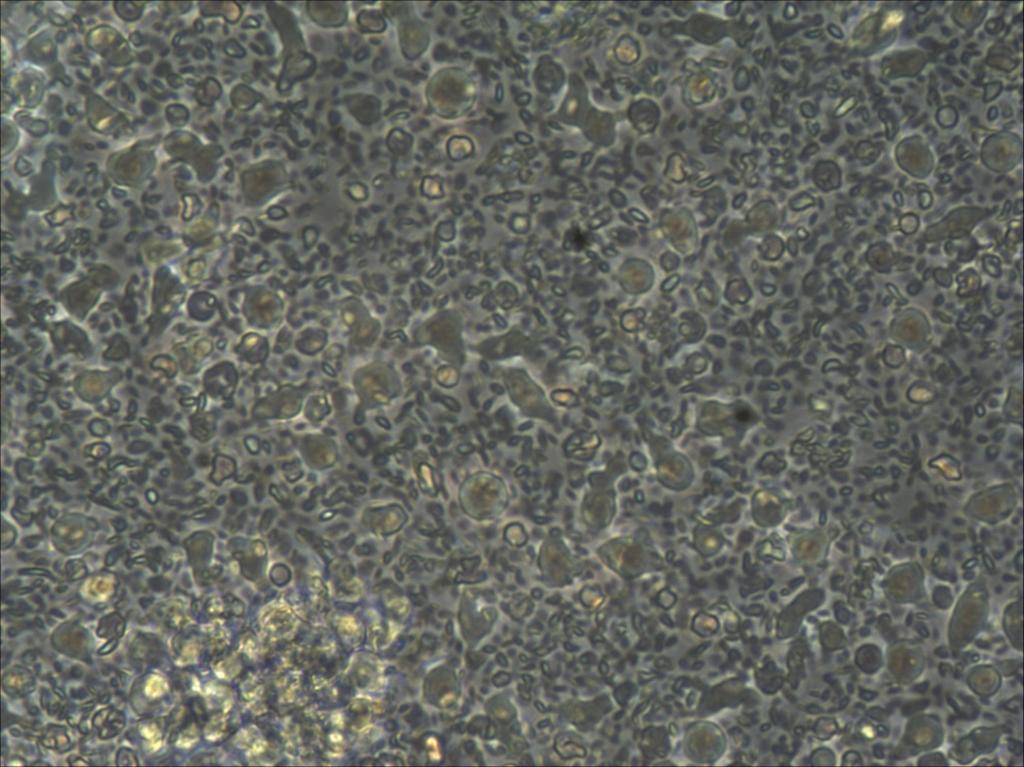

| ±¾ÈËÊÇ´ÓÁùÔ·ݿªÊ¼×ÅÊÖÆêѪ¼ä³äÖʸÉϸ°ûÅàÑø£¬¸Õ¿ªÊ¼ÎÛȾµÄ»ú»áºÜ¶à£¬ÒòΪÔÚÅàÑø»ùÖÐûÓÐʹÓÿ¹ÉúËØ£¬µ«Ò²ÅàÑø³öÔ´ú²¢´«´úÖÁµÚÈý´ú£¬ÒòΪûÁôÖÖ½á¹ûϸ°û´«´ú¹ý³ÌÖÐËÀÍö¡£½Ó׎øÐÐÏÂÒ»²½µÄ·ÖÀëÅàÑø£¬½á¹ûϸ°û¸Õ¿ªÊ¼Éú³¤½ÏºÃ£¬ËæºóÖÁÈýÖÜ×óÓÒϸ°ûÈÔÊôÓÚÔ²ÐΣ¬³¤ËóÐÎϸ°û£¬±âƽϸ°û·Ç³£ÉÙ£¬Ðü¸¡Ï¸°ûÔö¼Ó£¬ÓеÄϸ°û¿ªÊ¼ËéÁÑ£¬²»¾ÃÐü¸¡Ï¸°û¸ü¶àÁË£¬ËæºóÅàÑø°åÖÐËùÓÐϸ°û¶¼ËÀÍö¡£ÎÒÏëÎÛȾÒѾ¿ÉÒÔÅųý£¬ÏÖÔÚ²»ÖªµÀÆäËûÔÒòÊÇʲô¡£ÎÒÓõĺ¬15%̥ţѪÇåµÄDMEM/F-12£¬Ç°²»¾Ã¼ÓÈë¹ý¹È°±õ£°·¡£ÏëÄÄλ¸ßÈ˰ïæָµãÏ¡£ |

| ÆêѪ¼ä³äÖʸÉϸ°ûÊÇÌù±ÚÉú³¤µÄ£¬ÎÒÑøµÄÖ»ÊÇÔÓϸ°ûºÜ¶à£¬¶øÇÒ³¤ÌõÐεģ¬×îÖÕ²»ÔöÖµ£¬Öð½¥ÍÑÂ䣬ºÜÊÇÓôÃÆ°¡¡£ |